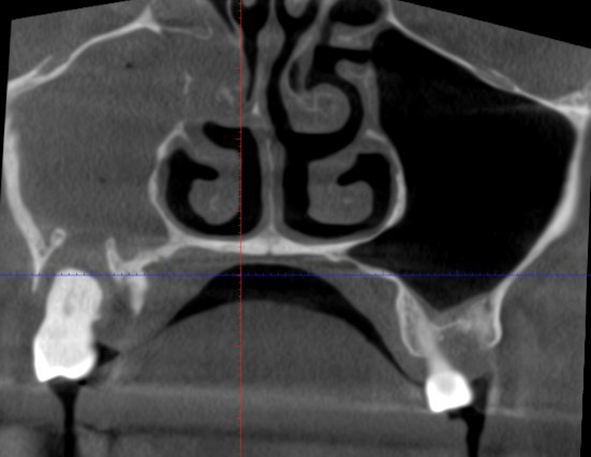

Это верхнечелюстная пазуха, снимок должен быть практически симметричным, и чёрные области должны быть с двух сторон. Но слева на снимке пазуха как будто ретуширована серым:

Это воспалённая слизистая при обострении хронического гнойного гайморита. Пузырьки, скорее всего, воздух. Классический одонтогенный гайморит. Причём с таким бесполезно бежать к отоларингологу, он не поможет. Посмотрите на эту невероятную красоту природы: ворота в пазуху проделал зуб. На зубе был воспалительный процесс (надо было чистить зубы, скорее всего, всё началось с кариеса или камня, попавшего под десну), он перекинулся на корень. Я не берусь утверждать точно, но всё указывает на то, что пациент перетерпел зубную боль до момента, когда нерв оказался разрушен. Дальше, собственно, воспаление разрушило дно пазухи.

Мораль: чистите зубы, не будет болеть нос и другие органы, не будет вот такого гайморита и хронического насморка. Ходите хотя бы раз в полгода к стоматологу на профилактику, потом не будете платить за новую челюсть. В случае этого пациента — увы, не только челюсть.

Почему я думаю, что пациент именно перетерпел? Потому что у этого зуба нет антагониста, нажимать было не больно, и каждый приём пищи он не страдал от дикой боли. К нам он обратился с температурой и головной болью. Точнее, в целом в больницу он обратился с таким анамнезом, а нам его уже передали коллеги. Воспалительный экссудат начал давить дальше, заболела голова.